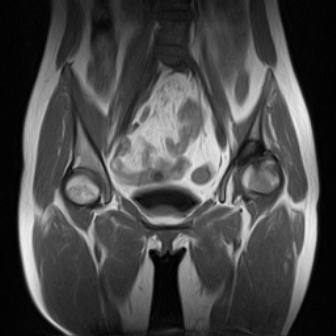

请看看我的片子,我得的什么病,该怎么治疗?谢谢[img][/img]

片子不全,应该是左侧股骨头无菌坏死,右侧似乎没问题,到正规医院治疗,千万别看广告去小医院,吃中药什么的,都是骗人的(说了也白说,百分百都得让人骗点钱才甘心。)

应该是左侧股骨头无菌坏死